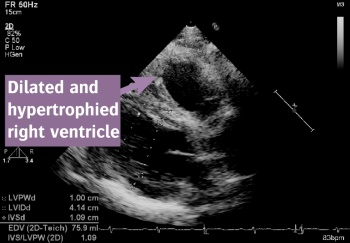

Figure 1: ECHO image of the patient's heart

ECHO revealed a hypertrophied and hypokinetic dilated right ventricle with marked trabeculations and evidence of pulmonary hypertension and right ventricular pressure overload. There was mild-to-moderate tricuspid regurgitation.

Left ventricular systolic function was preserved. There was moderate left ventricular hypertrophy and diastolic dysfunction. These findings were consistent with a history of sub-optimally controlled systemic hypertension. There was no significant left-sided valvular disease.

ECHO and electrocardiographic evidence of right ventricular dysfunction and pulmonary hypertension in an unusually somnolescent patient raised the possibility of obstructive sleep apnoea as a unifying diagnosis.

Sleep apnoea can cause pulmonary hypertension which, over time, results in right ventricular hypertrophy dilatation and ultimately right heart failure as described above.